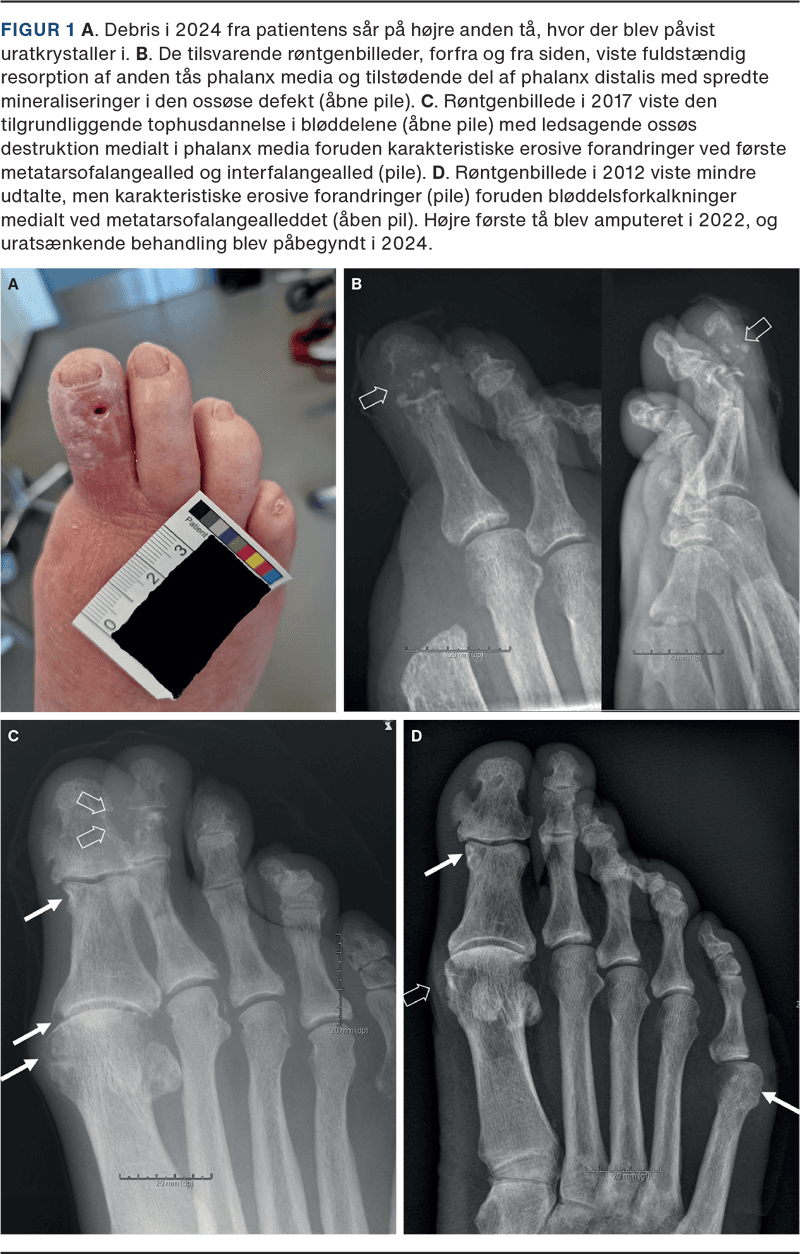

En 88-årig mand med DM2, hypertension, hyperkolesterolæmi, nedsat nyrefunktion og atrieflimren, og som var ikkeryger og uden alkoholoverforbrug, blev i 2005 undersøgt af neurolog pga. stikkende smerter under fødderne, men der var ingen tegn på neuropati. Patienten blev udredt i 2019 hos reumatolog pga. smerter i fødder, men uratsænkende behandling blev ikke iværksat. P-urat var i hele perioden 0,44-0,55 mmol/l. I 2012 havde han haft et forløb i diabetesambulatorium pga. sår over højre femte metatarsofalangeal (MTP)-led, som blev behandlet med sårpleje og langvarig antibiotikakur indtil opheling. Patienten var hos fodkirurg i 2017 med sår på højre anden tå, hvorfra der blev udtømt »tophusmateriale«. I 2022 opstod et nyt sår på højre første MTP-led, som blev behandlet med amputation af første tå. Der blev beskrevet »en del tophusmateriale« under operationen. Gentagne røntgenundersøgelser af fødderne viste fra 2012 tiltagende erosioner foreneligt med AU, men fortolket som infektion (Figur 1).

I 2024 blev patienten genhenvist til diabetesfodsårsambulatorium pga. recidiv af fodsåret på højre anden tå. Han gik sædvanligvis med træsko, der blev udskiftet til aflastende fodtøj. Der var ikke fejlstillinger eller kallositeter i foden. Distal blodtryksmåling viste, at højre tås tryk var kritisk lavt på 18 mmHg, og der var ingen fornyet karkirurgisk behandlingsmulighed. Fodstatus viste vibrationssans på 20 volt på begge fødder, bevaret stillingssans, ophørt kulde-/varmesans og følesans svækket, men ikke ophørt. Der blev i september 2024 udpresset grynet tandpasta-lignende materiale fra fodsåret, der for første gang blev undersøgt med polarisationsmikroskopi med påvisning af talrige nåleformede dobbeltbrydende uratkrystaller og dermed sikker diagnose af toføs AU. Patienten blev henvist til reumatolog, og uratsænkende behandling blev indledt. P-urat faldt fra 0,54 til 0,28 mmol/l efter to måneders behandling med allopurinol, men den kliniske effekt og svind af tophi kunne først forventes efter mange måneder.

Diagnosen AU er vanskelig, men røntgenbilleder kan give et godt fingerpeg i de sene toføse stadier med fodsår (Figur 1) [5]. Det er en god idé rutinemæssigt at undersøge for uratkrystaller, når der samtidig laves mikrobiologisk undersøgelse på ledvæske, operationsmateriale eller såroprensning. UL-undersøgelse og især dual-energy CT er andre muligheder for at påvise urataflejringer uden punktur.